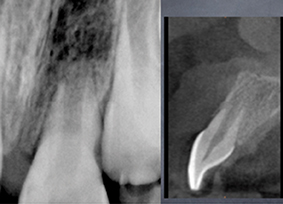

Viendra ensuite le tour de Stéphane Simon qui exposera trois nouveaux concepts dans le domaine de l’endodontie.

Il débutera sa conférence par une présentation en avant-première d’un nouveau système d’irrigation en continu avec une activation en un seul temps. Si jusqu’alors les praticiens procédaient de façon « artisanale », ce nouvel appareil, conceptualisé par Stéphane Simon lui-même, permet d’irriguer tout au long de la préparation du canal de la racine. Deuxième nouveauté en endodontie : l’obturation du système canalaire recourant au concept de monocône. Stéphane Simon présentera les nouveaux matériaux biocéramiques qui permettent de mettre en application ce concept. Il expliquera comment un seul matériau peut remplir et rendre hermétique le canal. Le troisième concept sera basé sur l’ingénierie tissulaire en endodontie régénérative.

- Innovation matérielle et conceptuelle en endodontie

par Stéphane Simon

La plus-value tient en deux mots : nouveautés et révolutions. Les concepts, présentés par trois grands noms de la profession, sont révolutionnaires voire avant-gardistes dans le mode de la dentisterie. Pour ne donner qu’un exemple, l’intervention de David Nisand va à l’encontre des idées reçues en implantologie. Quant à Stéphane Simon et Gil Tirlet, ils repensent les techniques actuelles.

Ils expliqueront comment conserver la pulpe voire la façon dont le praticien peut la régénérer au lieu de la remplacer. Les techniques adhésives qui dépassent largement ce que nous avons vu jusqu’à maintenant, permettent la restauration de délabrements partiels, mais aussi de grands délabrements sur des dents dépulpées ou non, mais avec des pertes de substances importantes.